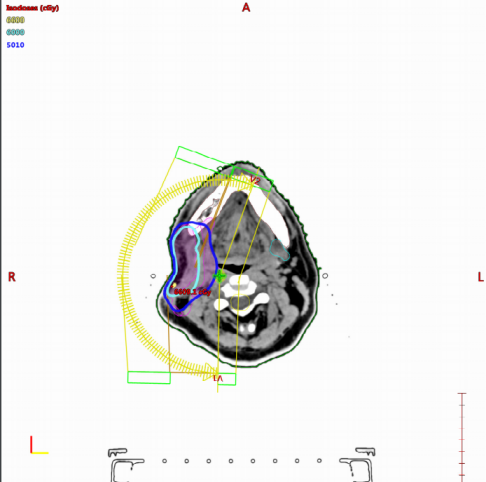

2024-03-20开始行肝转移灶放疗,采用6MV-X线,设VMAT,采用ABC-DIBH呼吸门控技术,处方剂量给予:95%PTVp 40 Gy/5 F。隔日一次。

图片13.png

2024-03-27开始行胸膜转移灶放疗:放疗采用6MV-X线,设VMAT,采用ABC-DIBH呼吸门控技术,处方剂量给予:95%PTVp 50 Gy/5 F。隔日一次。

图片14.png